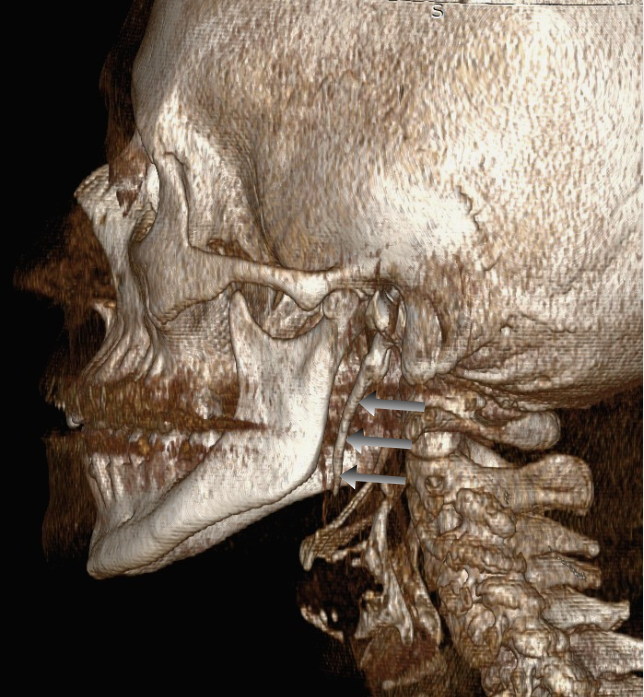

- 3D Αξονική Τομογραφία (CT) σπλαχνικού κρανίου: Θεωρείται η εξέταση εκλογής (gold standard), καθώς επιτρέπει την ακριβή μέτρηση του μήκους της απόφυσης και τον προσδιορισμό της γωνίας της σε σχέση με τις γύρω δομές.